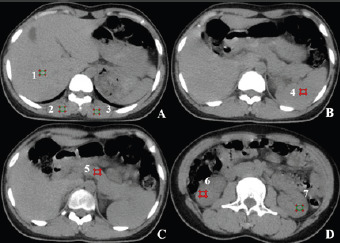

Objective: This study aimed to investigate the impact of Clear View dual-domain iterative reconstruction (IR) technology on the quality of low-dose abdominal CT images and to determine the optimal weight ratio to optimize image quality.

Methods: We studied 40 patients (28 males, 12 females, aged 19-69) undergoing low-dose abdominal CT scans (CTDI = 5.32 ± 0.89 mGy). The scanning parameters were set as follows: tube voltage of 120 kVp, tube current modulation based on Signal to Noise Ratio (SNR) at 0.5 mode (O-Dose automatic tube current modulation technology), pitch of 0.9, rotation time of 0.6 s/r, matrix size of 512 × 512, and collimation width of 16 × 1.25 mm. We applied Clear View IR with four weight ratios (20%, 40%, 60%, 80%) and filtered back projection (FBP). Conventional scanning uses with 120 kVp, 280 mAs, pitch of 0.9, rotation time of 0.6 s/r, matrix size of 512 × 512, and collimation width of 16 × 1.25 mm. Conventional dose abdominal CT scans (CTDI = 11.95 ± 0.00 mGy).CT values, standard deviations (SD), signal-to-noise ratio (SNR), and contrast-to-noise ratio (CNR) were measured for liver, spleen, pancreas, kidneys, and erector spinae muscles. Two deputy chief physicians blindly evaluated image quality on a 1-5 scale. Statistical analysis was done using SPSS 22.0 with P < 0.05 considered significant.

Results: Subjective evaluations revealed the highest diagnostic score with a 40% Clear View reconstruction weight ratio. Higher weight ratios significantly reduced subjective image noise, with the highest noise scores at 80%. Moreover, compared to FBP, especially Clear View reconstruction weight ratios of 20% to 60%, significantly improved the image quality of abdominal solid organs, reducing image artifacts and improving diagnostic acceptability (P < 0.05). Objective evaluation showed that with increasing Clear View reconstruction weight ratios, image noise SD values decreased, while SNR and CNR values increased, and the differences in SD, SNR, and CNR for different reconstruction weight ratios of abdominal solid organs were statistically significant (P < 0.05).

Conclusion: Compared to FBP algorithm, Clear View demonstrates greater potential in low-dose abdominal CT, effectively reducing image noise and artifacts while maintaining image clarity. Based on combined subjective and objective evaluations, a 40% Clear View reconstruction weight ratio provides optimal image quality for abdominal solid organs.